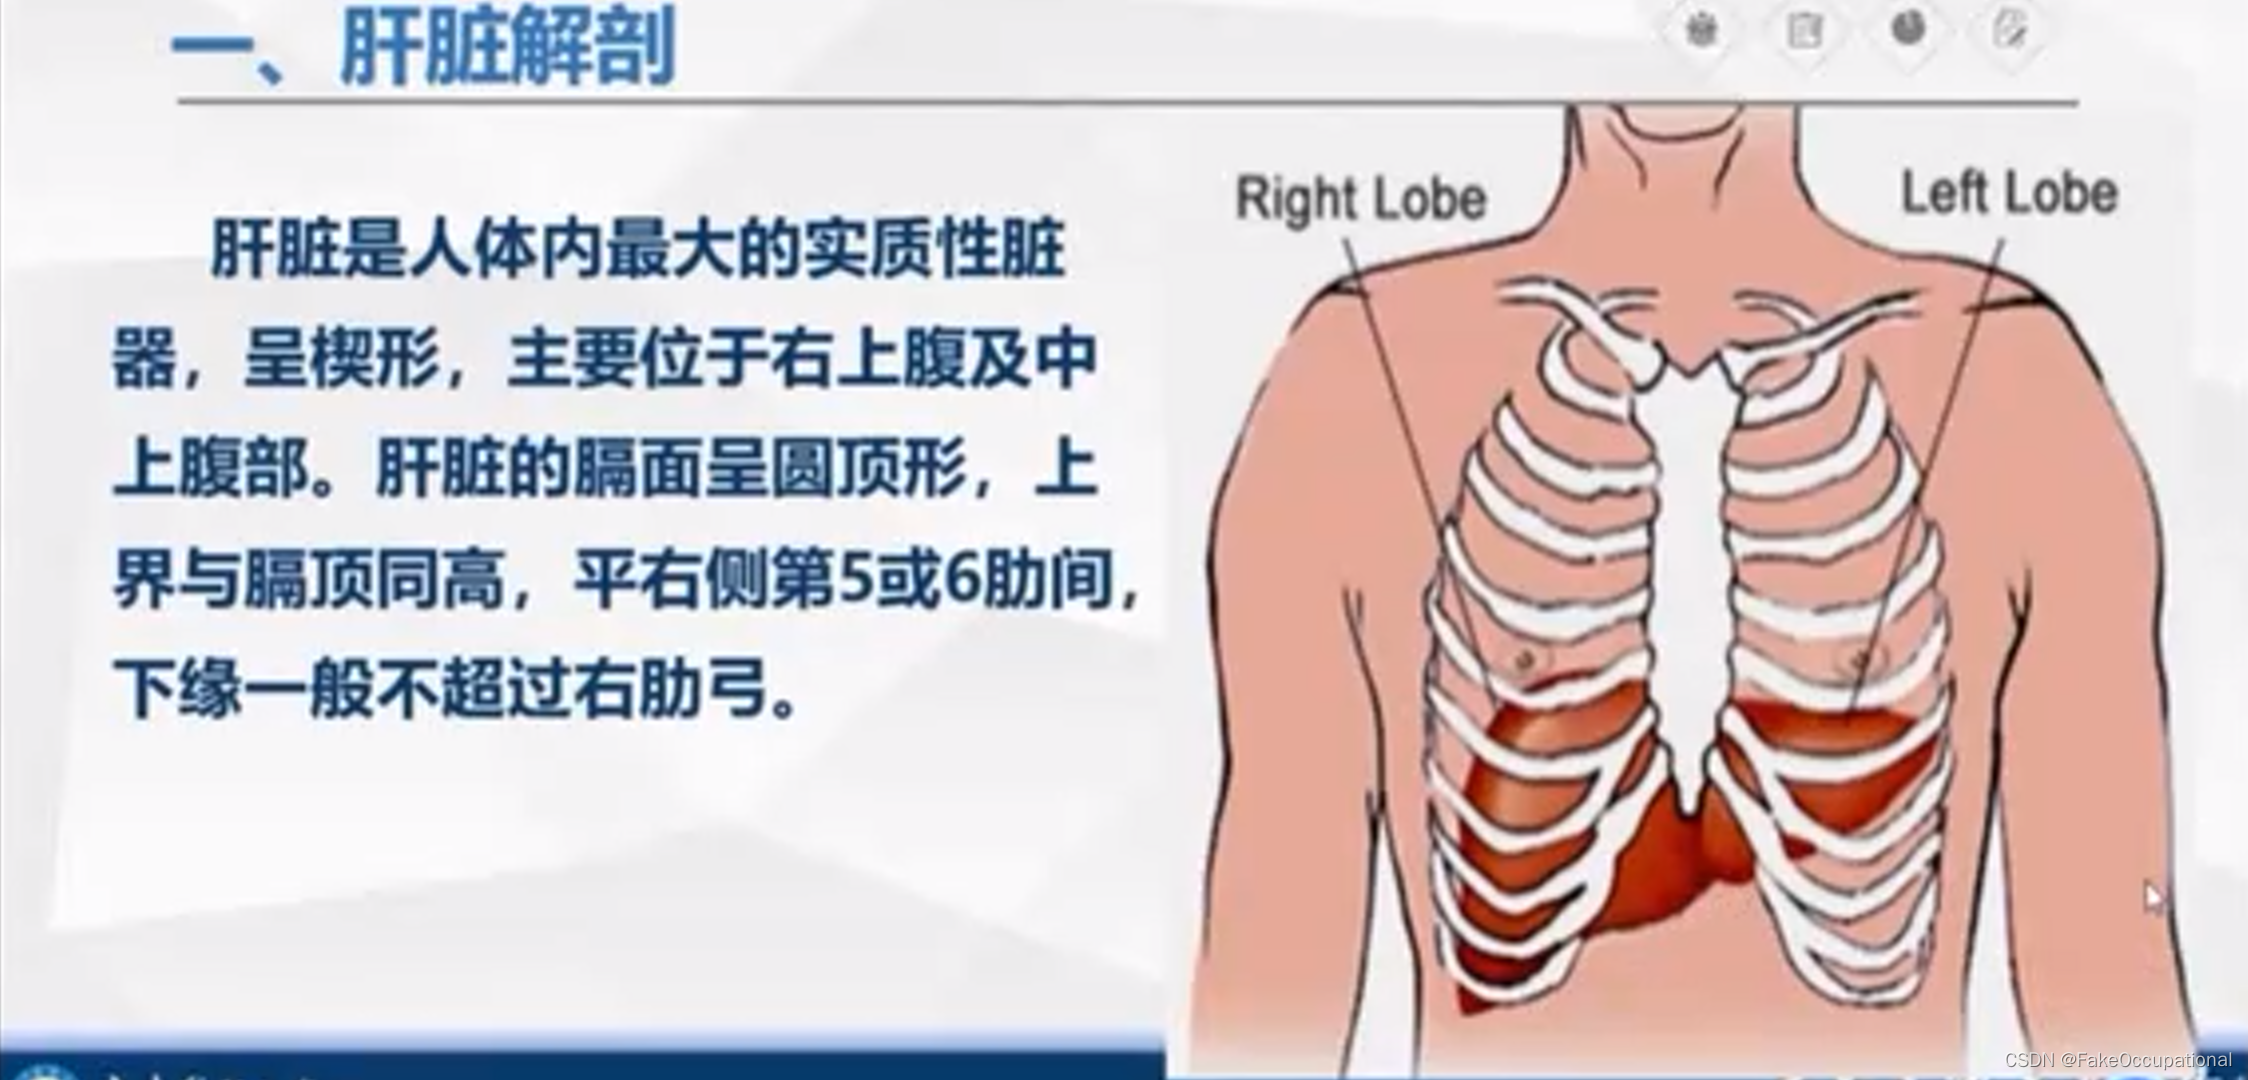

肝脏解剖概要

肝脏超声检查技术

正常肝脏超声表现